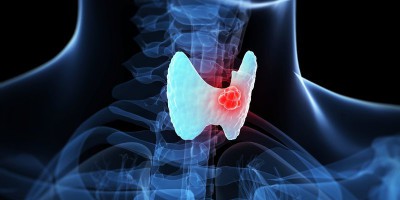

Quản lý ung thư tuyến giáp thể nhú

Việc điều trị và hiểu về cách thức quản lý ung thư tuyến giáp thể nhú sẽ có sự khác biệt so với các type ung thư giáp và giai đoạn bệnh. Phát hiện...